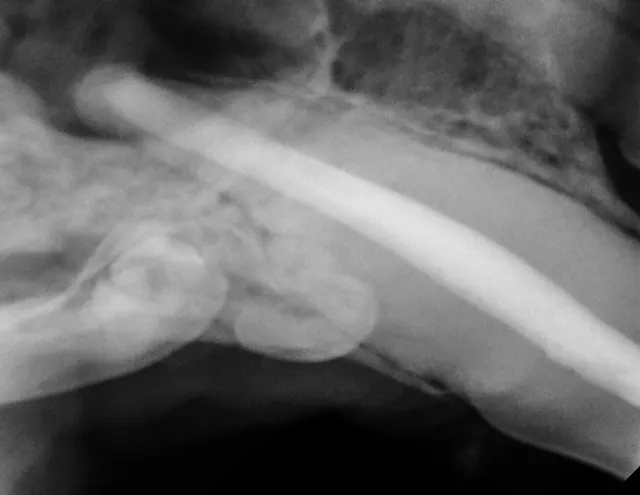

FIGURE 1A

Resorbing deciduous (primary) left mandibular fourth premolar.

2. Reduce

In rare forms of tooth resorption, the root’s dental hard tissue is replaced by bone. The root will appear to have less radiopacity when compared with adjacent normal roots. The remaining crown’s height can be reduced to a subgingival level via amputation and sutured closed.